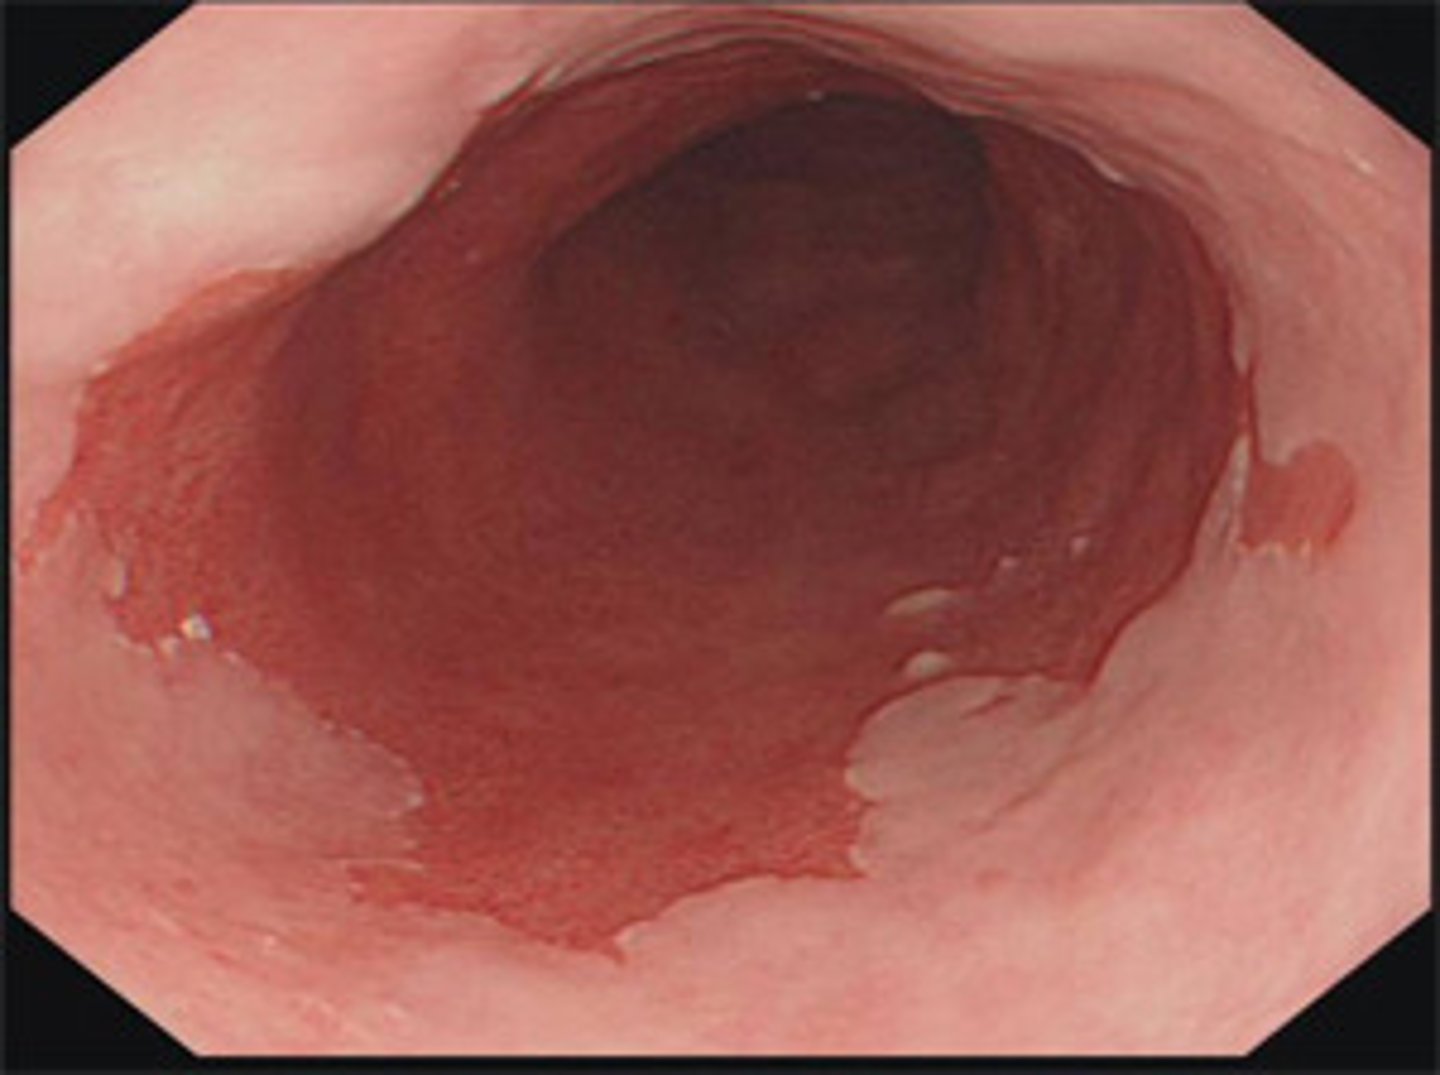

Jim is a 70 year old white man with GERD. He has had GERD for the past 6 years. You decide to screen him for Barrett's esophagus since he has two or more risk factors.

What test do you run?

What do you need to order to confirm the diagnosis?

What do you treat him with?

1.) Endoscopy

2.) Biopsy is needed for diagnosis

3.) Long-term PPIs once or twice daily to control reflux symptoms

In a patient with barrett's esophagus, how often should you perform an endoscopy if no dysplasia is present?

Every 3-5 years

Amy is a 51 year old woman with barrett's esophagus. She has high grade dysplasia and adenocarcinoma. What therapy should she undergo?

Endoscopic therapy

She needs to have an endoscopy every 3-6 months.

Richard a 65 year old man with Barrett's esophagus has low grade dysplasia. How often should he receive endoscopic therapy?

Every 6-12 months

Barrett's esophagus

What is this image of? It is salmon colored.